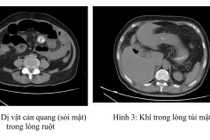

Tắc ruột do sỏi túi mật, “quả bom nổ chậm” ít ai ngờ

Sỏi mật để lâu có thể gây ra rất nhiều biến chứng nguy hiểm như viêm thủng túi mật vào tá tràng và rơi xuống ruột non gây tắc...

Ca lâm sàng “hiếm gặp” từ cơn đau bụng bất ngờ